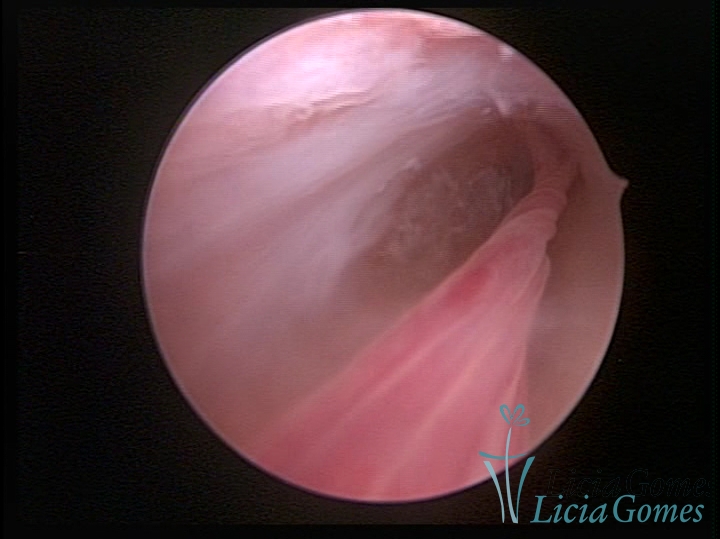

Panoramic view of a cesarean section scar with a non-absorbable suture for 30 years.